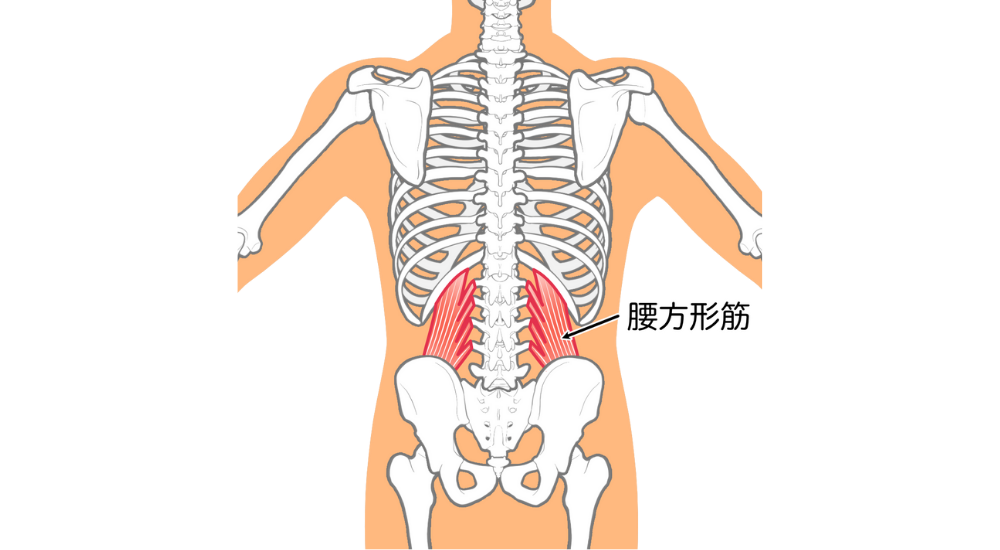

- 腰方形筋: 腰の側面。反り腰に伴う腰の不安定性やバランスの崩れで硬くなりやすいです。